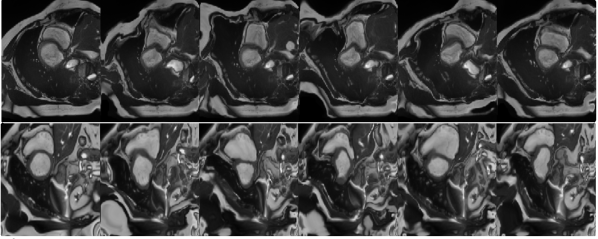

(a) image ()

(b) deformation field

(c) transformed

over image (v)

image ()

(i) Transformed images are obtained by applying deformation fields produced by Generator .

(ii) Transformed images are obtained by applying random elastic deformations.